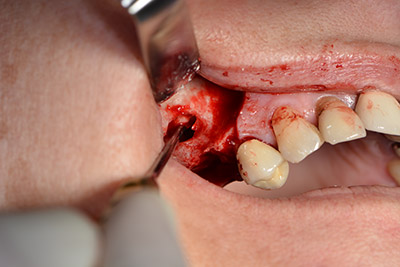

En el siguiente paso se efectúa la elevación del suelo del seno maxilar, a la vez que se coloca el implante. Para la fenestración lateral de la pared del seno maxilar Implantmed también cuenta con un ajuste predefinido en la primera posición.

La ventana se crea a una velocidad de 35.000 rpm y, a continuación, la membrana de Schneider se prepara en sentido craneal (figuras 13 a 14).

Acto seguido, se coloca el implante y se estructura el hueso. Dado el tamaño del aumento, en el caso que nos ocupa se utilizó hueso autógeno, que había surgido como virutas de fresado en el implante 16 y en la fenestración 14 y se había recogido con un colector óseo, y se combinó con material de reemplazo óseo.

Una membrana reabsorbible formó la barrera en sentido bucal y cubrió el aumento. Por último se procedió a la sutura de modo que no penetrara saliva (figuras 15 a 19).